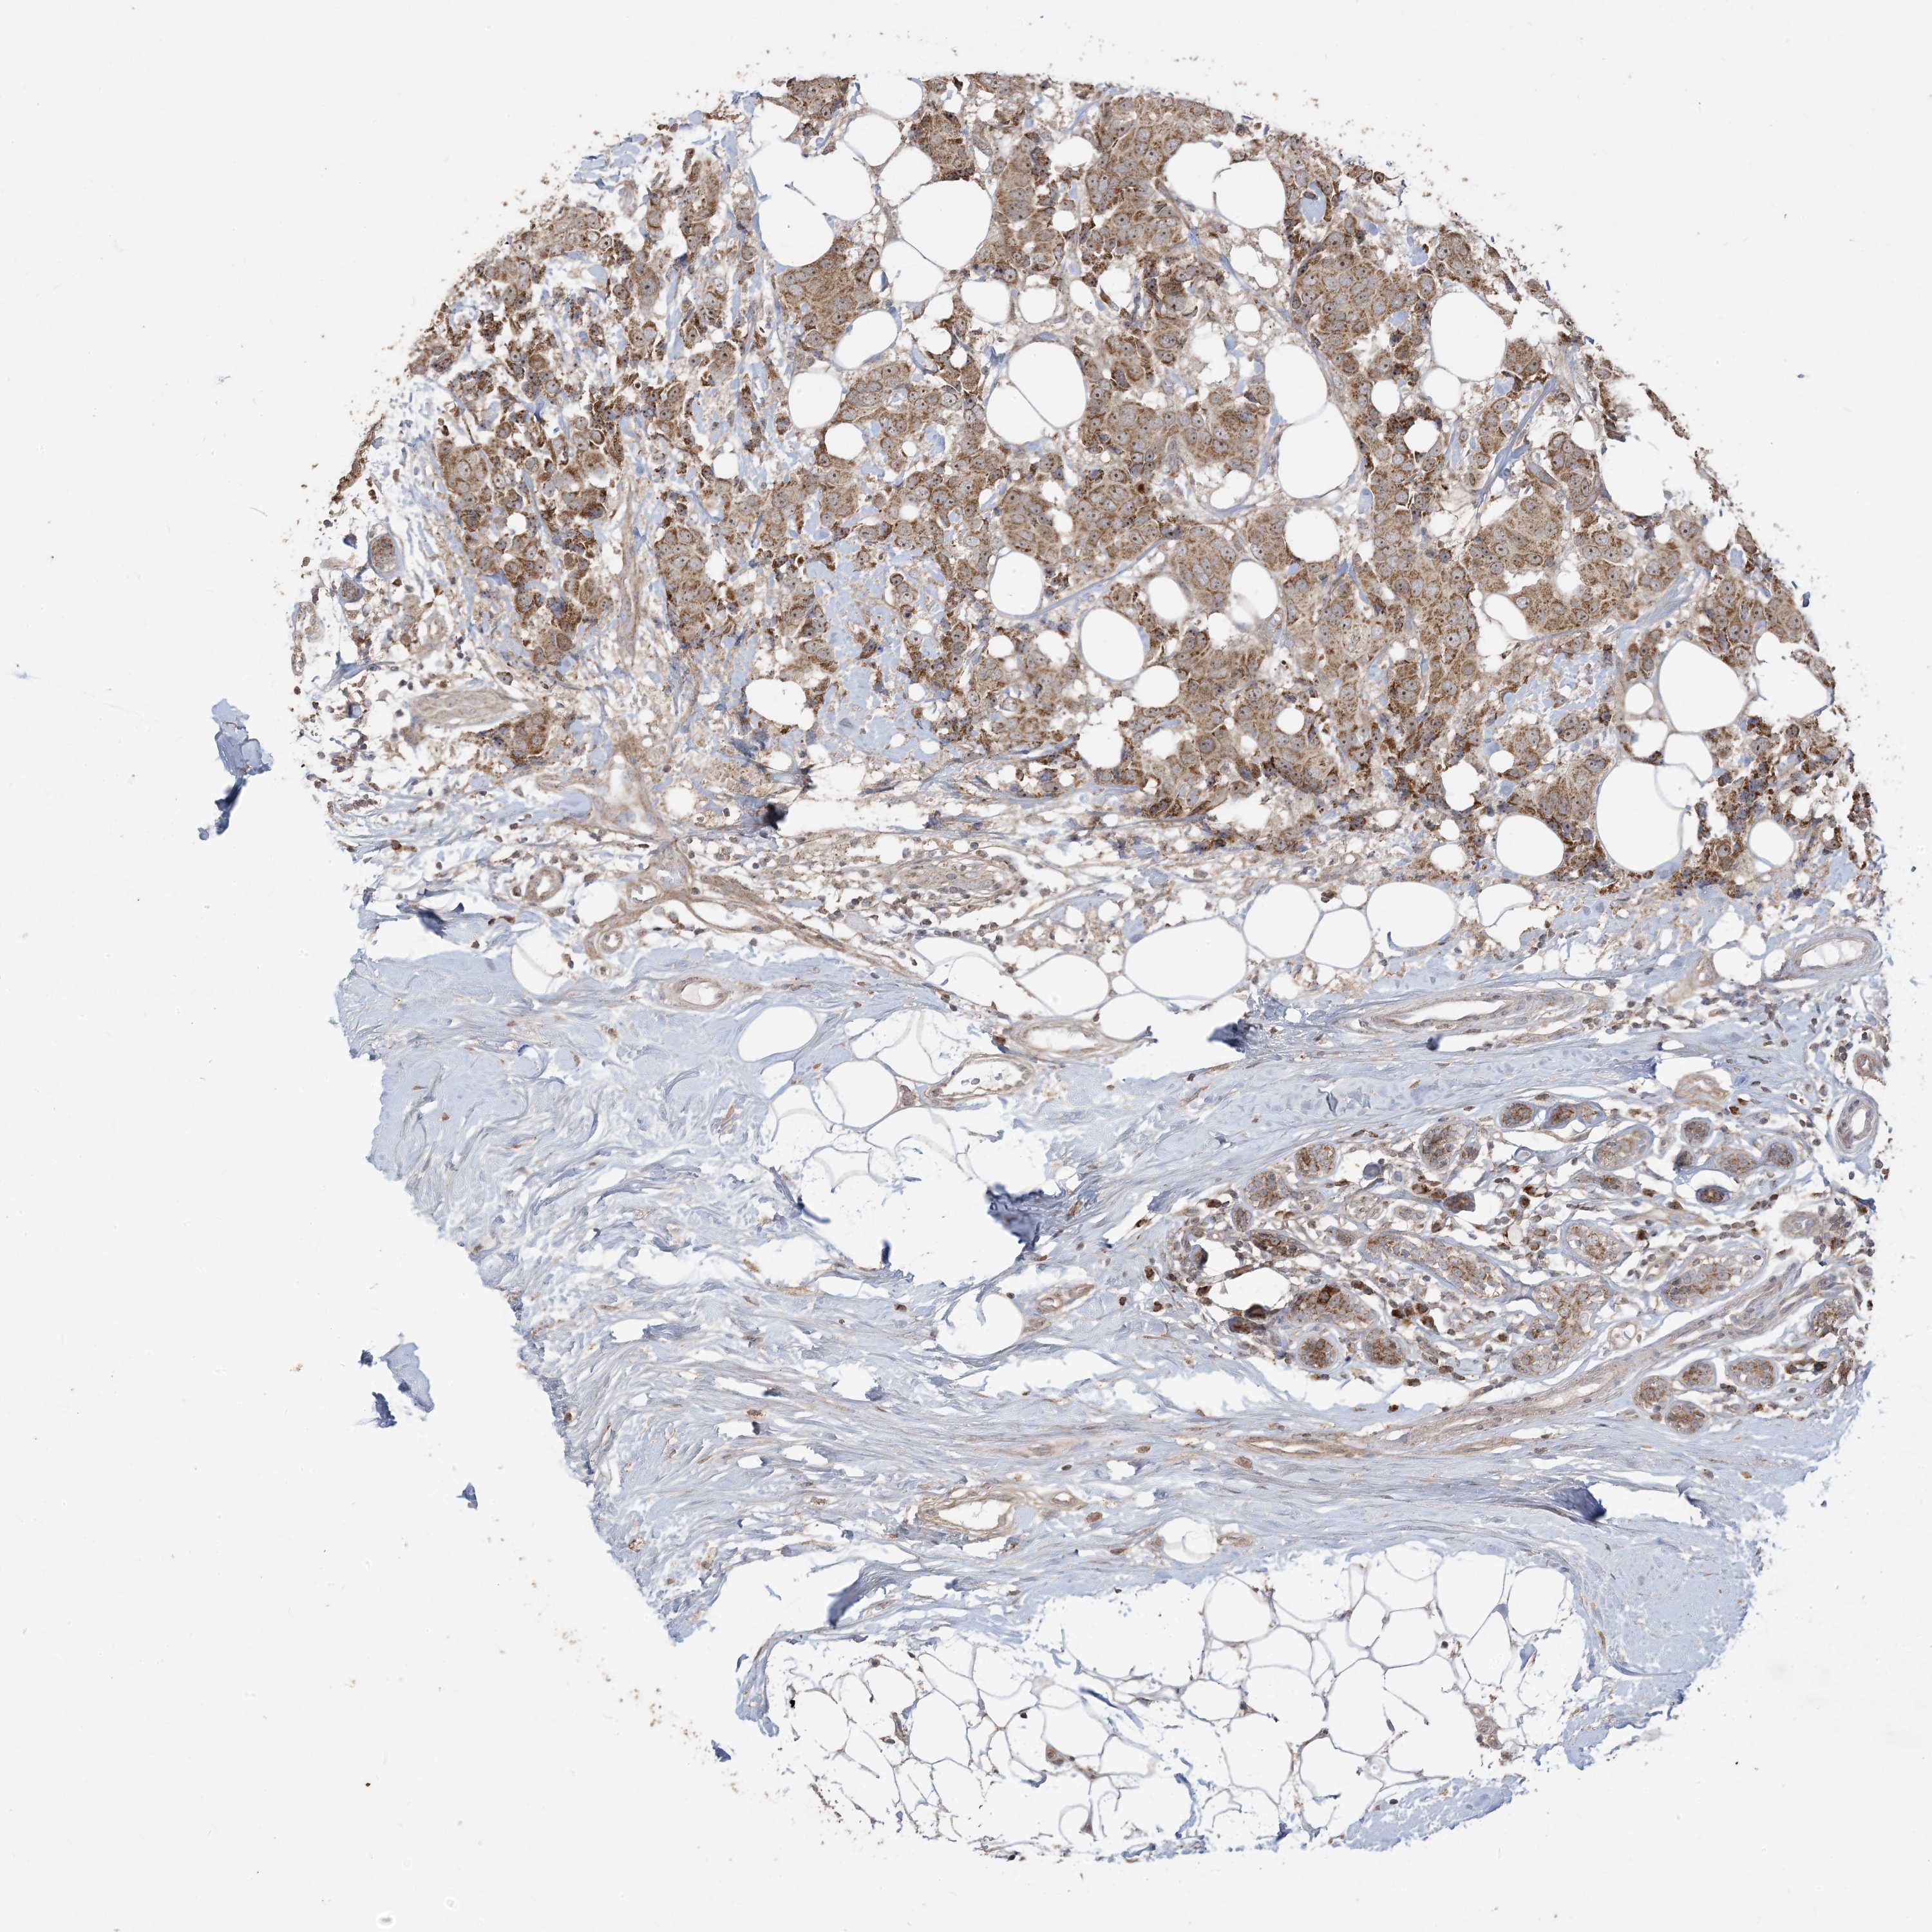

CANCER BREAST CANCER Show tissue menu

BRCA TCGA BRCA VALIDATION PROTEIN EXPRESSION